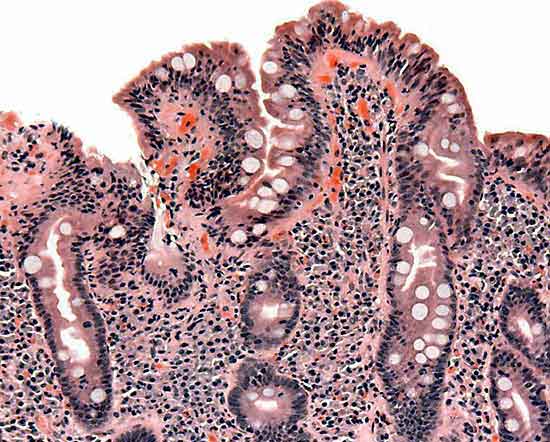

Boom di ‘Mici’ tra i bambini. Le malattie infiammatorie croniche dell’intestino, colite ulcerosa e Crohn, colpiscono sempre prima con un aumento dei baby-pazienti che negli ultimi anni arriva a superare il +50%.malattie_villi L’allarme è stato lanciato a Vienna, dove oggi si apre l’ottavo Congresso dell’Ecco (European Crohn’s and Colitis Organisation). I numeri di queste patologie tra i giovanissimi sono un’emergenza sempre più grave nei Paesi industrializzati, hanno avvertito gli esperti durante un incontro promosso dall’Efcca (Federazione europea delle associazioni per la malattia di Crohn e la colite ulcerosa), soprattutto perché in età pediatrica Crohn e colite sono molto più aggressivi, con un maggior rischio di complicanze e interventi chirurgici.

Nella caccia alla scintilla che infiamma l’intestino dei malati di Crohn e colite ulcerosa “siamo ancora molto lontani dalla verità”, ammette Kohn. “La ricerca si concentra sulla comprensione dei meccanismi che, alterati, provocano una reazione immunitaria abnorme e mantenuta nel tempo a qualcosa con cui la mucosa intestinale viene a contatto”, aggiunge l’esperta. “C’è qualcosa che si inceppa e innesca il passaggio da un’infiammazione fisiologica a un’infiammazione patologica”, precisa Gionchetti. Anche se, soprattutto per quanto riguarda il Crohn, ogni paziente è una storia a sé.